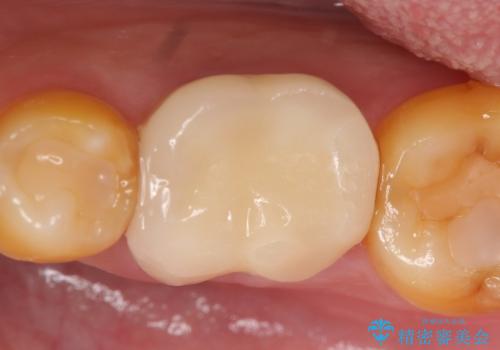

- 当院で前歯を治療中の患者様でしたが、左下1番奥の金属のつめものが外れたため、奥歯の治療もご希望されました。

その歯のすぐ後ろには埋まっている親知らずがあり、歯周ポケットも8mmありました(正常値3mm以下)。

このままでは適合のよい被せものを製作するのは難しいため、親知らず抜歯を行い、歯肉の位置が変化するのを待ってから被せものを製作しました。

外れたつめものの境目は歯肉の下でしたが、親知らずの抜歯を行うことで、歯肉の位置が変化して、境目が見えるようになり、適合のよい被せものを製作することができました。

今回のようなケースは、親知らず抜歯が有意義になります。